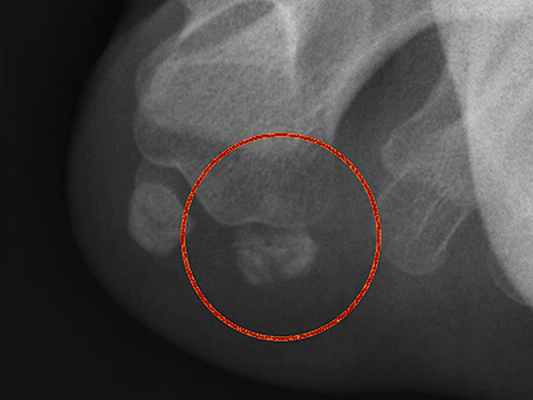

Здесь как раз выраженный сесамоидит. Отмечаются изменения в трабекулярной структуре кости

Реже, но тоже довольно часто пациенты жалуются на онемение в большом пальце стопы. Это можно объяснить вовлечением в патологический процесс идущего рядом кожного нерва.

Диагностика обычно не несет каких-то проблем. При осмотре выявляется боль с подошвенной поверхности плюснефалангового сустава большого пальца. Обязательно проводится рентгенография, чтобы отличить такие заболевания как подагра, артроз, подвывих большого пальца при поперечном плоскостопии. А также важное — перелом сесамовидной кости имеет сходные симптомы.

Перелом сесамовидной кости. Нужно помнить, что иногда выявляется «дольчатая» сесамовидная кость. Обычно состоящая из двух (бывает больше) элементов. Но в таком случае на рентгенограмме видны ровные и гладкие края «долек»